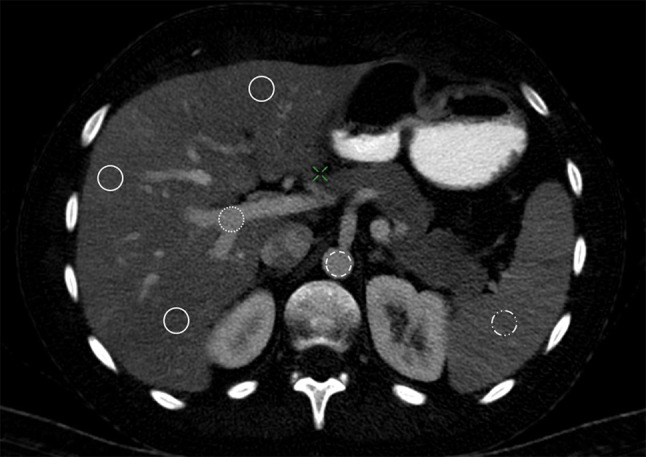

The iodine concentration of the liver parenchyma was measured using the same three ROIs in 5-mm-thick portal-venous iodine images, assuring an exact match of the measured areas. Two further ROIs for the measurement of the iodine concentration were placed in the aorta, and portal vein, both at the level of the coeliac axis. The diameter of these two ROIs was adapted to the vessel lumina, enclosing the largest possible area, respectively. The positioning of all ROIs is shown in Fig. 2. All measurements were performed by an experienced radiologist, who was blinded to pre-existing clinical information.

Fig. 2.

Placement of the ROIs in a transversal plane dual-energy CT quantitative iodine image of a 55-year-old male individual. The portal venous phase DECT iodine image corresponds to the coeliac axis and shows a total of six ROIs. Three ROIs are placed in the hepatic tissue (continuous line), one in segment 3 in the left hepatic lobe and two in the right hepatic lobe in segments 4b and 7. One ROI (dotted line) is in the portal vein, and one ROI (dashed line) is in the aorta. Another ROI is placed in the spleen tissue (dotted and dashed line)